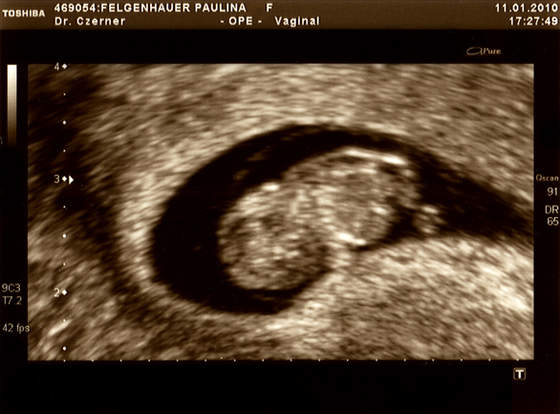

Dzidziolek rośnie ma 2,55 cm, co wg usg potwierdza 9w3d (wiec ciąża trochę młodsza ze względu na późną owulacje- termin zostawiam bez zmian bo i tak będzie sie zmieniał)Serduszko bije 163/min .